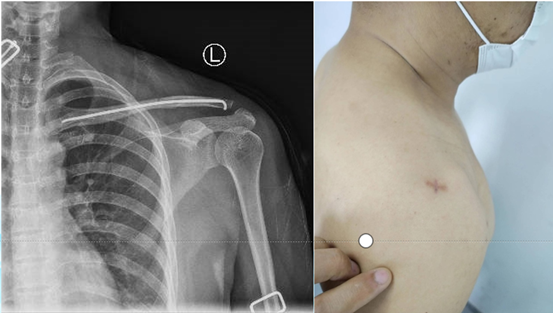

上图:CT三维重建技术

比如,现在我们普遍采用CT三维重建技术。手术前,我们就能在电脑上清晰地看到骨折的“立体地图”,进行虚拟手术规划;手术中,则借助“透视眼”一样的导航系统,让医生在屏幕上实时看到器械在骨骼内的精确位置。对于骨盆、脊柱等部位的复杂骨折,这些技术成为了安全手术的基石。

更值得一提的是,微创理念已深入人心。我们通过几个小切口,在特殊透视机和导航引导下,置入螺钉和钢板进行固定,大大减少了对患者正常肌肉和软组织的损伤。这意味着术后疼痛更轻、康复更快、感染风险更低。

1.通过术中三维影像让机器人“看清”骨折块的精确位置;

2.医生在系统上规划出最佳复位路径、螺钉植入的虚拟通道;

3.机械臂随后引导医生,经皮植入专门的复位工具,以微小力量轻柔地将错位的骨块“推”回原位;

4.在机器人导航下,通过几个仅5毫米的皮肤小孔,精准置入所有固定螺钉,全程无需切开暴露骨折区。

上图:传统锁骨骨折手术后愈合效果

上图:机器人参与锁骨骨折手术后效果

首例手术成功实施后,患者仅留下几个几乎看不见的小点,术后疼痛轻微,三天即顺利出院。这让我们深感欣慰。

这两年,我院开展该项手术300多例,已成为我院的常规治疗方式。这个“金点子”的落地,真正实现了锁骨骨折的精准、微创、美观治疗,让患者以最小代价获得最佳康复,这是医工携手为患者带来的切实福祉。